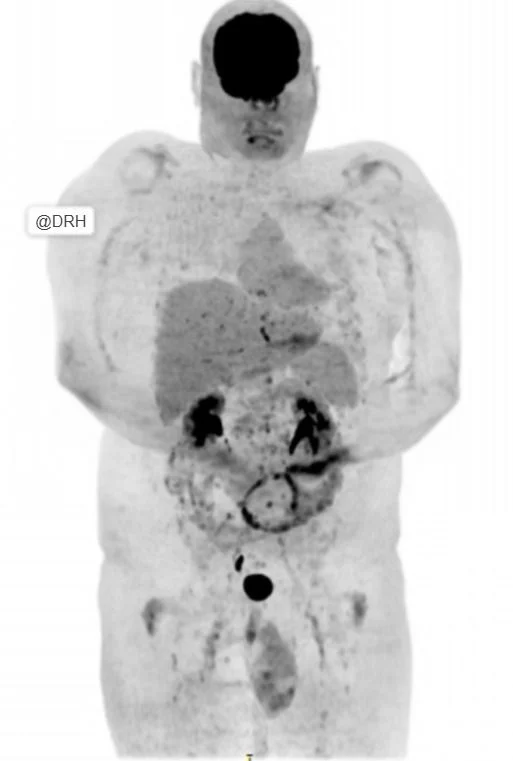

- Following systemic chemotherapy, response evaluation demonstrated:

- Near complete metabolic and morphological resolution of previously involved sites: Image B

Residual areas of uptake corresponding to a Deauville score of 4, consistent with a partial metabolic response

This case underscores a critical point in lymphoma management:

- Structural imaging alone may underestimate response

- Metabolic imaging provides the nuance needed for accurate response categorization.